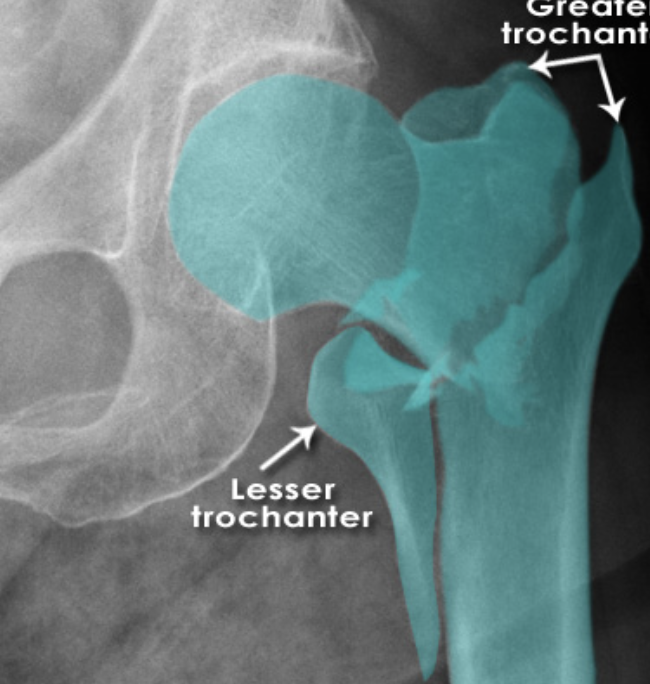

Describe the type of fracture depicted [1]

Intertrochanteric fracture

* A fracture line runs between the trochanters

* There is comminution with separation of the lesser trochanter

* Note the fracture does not involve the femoral neck